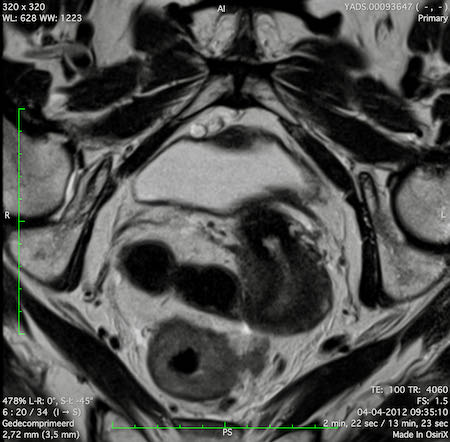

Hình ảnh

Các hình ảnh được cung cấp cho thấy ung thư biểu mô tế bào nhẫn với tình trạng dày lan tỏa thành trực tràng, hình ảnh bia bắn điển hình, và sự xâm lấn mỡ mạc treo trực tràng.